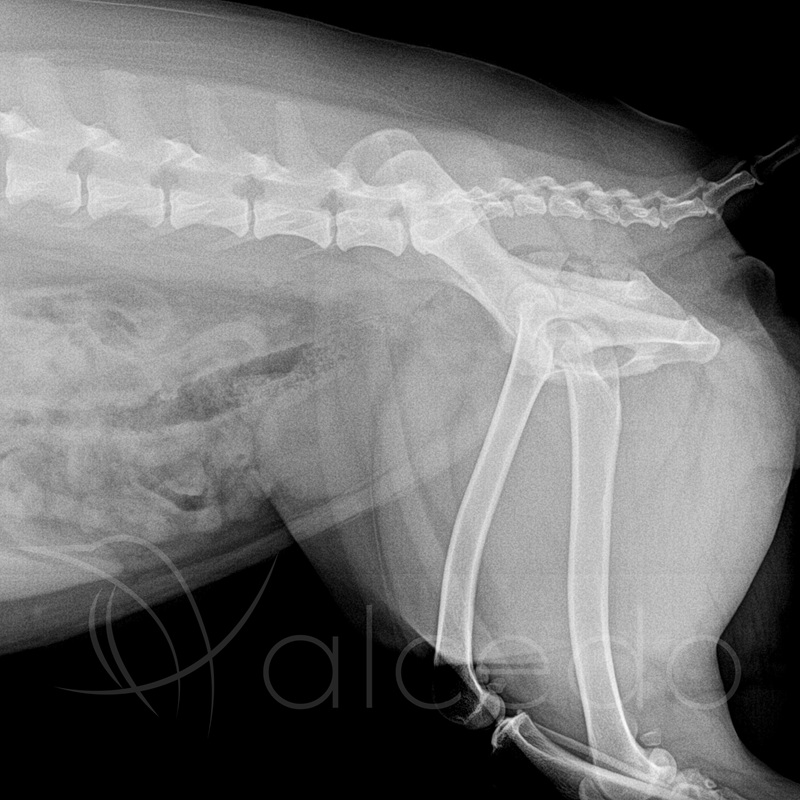

Cyfrowy aparat rentgenowski o bardzo wysokiej częstotliwości umożliwia błyskawiczne i szczegółowe radiogramy przy możliwie najniższej dawce promieniowania. Dzięki wszechstronnemu zakresowi parametrów diagnozuje subtelne złamania najmniejszych papug oraz precyzyjnie odzwierciedla zmiany w największych stawach największych psów. Ruchoma lampa i pływający blat pozwalają na wielopłaszczyznowe pozycjonowanie badanych struktur.

Cyfrowy detektor bezpośredni o rozmiarze piksela 140μm i o potężnej matrycy daje wysokiej rozdzielczości obraz niezbędny do skrupulatnej diagnostyki radiologicznej.